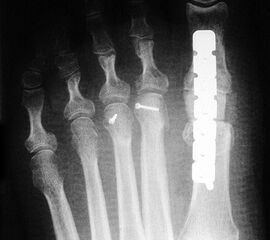

Die dorsoplantaren Röntgenaufnahmen zeigen eine Open-wedge Technik mit der normalerweise ein erhöhter intermetatarsaler Winkel gut zu korrigieren ist (Abbildung 3). Die Wirksamkeit einer Basisosteotomie ist umso größer, je proximaler diese durchgeführt wird. Je weiter distal die Osteotomie, umso geringer die Korrektur. Auf den postoperativen Bildern ist der distal unverändert große Abstand zwischen Metatarsale I und Metatarsale II erkennbar, bei gleichzeitiger Subluxation des Großzehengrundgelenks und dezentrierten Sesambeinen. Darüber hinaus finden sich initiale degenerative Veränderungen im Großzehengrundgelenk. Klinisch bestand eine hohe Weichteilspannung, bei verkürzter Extensor- und Flexor hallucis longus Sehne.  Daher wurde ein verkürzendes Verfahren zur Revision gewählt (Abbildung 4). Die Lapidusarthrodese stellt ein sehr zuverlässiges Verfahren zur Behandlung von Hallux valgus Rezidiven dar 9. Die Fusion des Tarsometatarsale-I-Gelenks kombiniert Stabilität mit einem hohen Korrekturpotenzial. Aufgrund der verfahrensimmanenten Verkürzung des ersten Strahls und der in diesem Fall bereits präoperativ vorhandenen Transfermetatarsalgie wurde die Entscheidung für eine verkürzte Weil-Osteotomie am zweiten bis fünften Strahl gefällt. Die Kombination beider Verfahren führte zu einem homogenen Metatarsale-Index und zu einer gleichmäßigen plantaren Druckverteilung 10. Die Hallux valgus interphalangeus Fehlstellung wurde mit einer Akin-Osteotomie korrigiert.